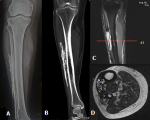

A 50-year-old male presented with a long-standing, slowly progressive, hard swelling over the anterolateral aspect of the right leg. He reported a history of snake bite to the same limb 20 years earlier, which was associated with severe local tissue injury. There was no history of recent trauma, constitutional symptoms, or clinical signs of active infection. Plain radiograph of the right leg demonstrated sheet-like intramuscular calcification along the lateral aspect of the tibia without cortical erosion or periosteal reaction. Non-contrast computed tomography (CT) revealed well-defined linear intramuscular calcifications with central areas of low attenuation suggestive of necrosis within the anterior compartment of the right leg. Magnetic Resonance Imaging (MRI) of right leg demonstrated linear sheet-like intramuscular areas of T1- and T2-hypointensity corresponding to calcifications, with heterogeneous central signal intensity involving the tibialis anterior muscle. The differential diagnosis of such radiological features in the lower limb include; myositis ossificans, soft tissue sarcomas, and chronic expanding hematoma. Myositis ossificans classically demonstrates a zonal pattern of peripheral mature ossification with central lucency on radiographs or CT, which is not identified in this lesion, as there is no organized cortical bone formation. Soft tissue sarcoma may present with irregular or amorphous calcifications, a solid enhancing soft-tissue component, and occasionally cortical erosion or periosteal reaction-features that are not observed in our case. Chronic expanding hematoma can show a well-defined capsule, internal fluid-fluid levels, and a hemosiderin rim on MRI. However, the plaque-like peripheral dystrophic calcification along a single muscle compartment is more typical of calcific myonecrosis. The absence of aggressive characteristics and the presence of fusiform compartmental involvement with sheet-like calcification support the diagnosis. Taken together, the imaging findings are most consistent with calcific myonecrosis rather than the above differentials.

Figure 1: A) X-ray of right leg demonstrating linear, sheet like, egg shell calcification in the soft tissue compartment laterally adjacent to fibula in the mid leg region showing no evidence of bone involvement or periosteal reaction; B) CT right leg coronal view demonstrating peripheral sheet-like calcification along the long axis of the limb within a fusiform intramuscular lesion; C, D) MRI right leg (coronal and axial views) shows a fusiform intramuscular lesion with low-signal peripheral rim and central T2 hyperintense calcified content